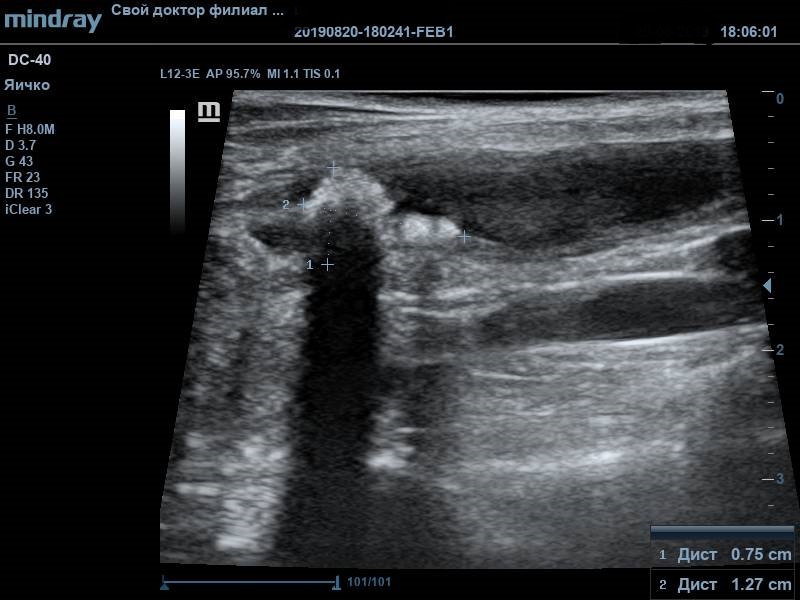

Во время УЗ-диагностики были обнаружены следующие изменения: неравномерное утолщение стенки мочевого пузыря (от 0,3 до 0,7см), слизистый слой гиперэхогенный. В содержимом мочевого пузыря присутствовал обильный крупнодисперсный осадок. В области мочевого треугольника визуализировалось пристеночное рыхлое ассиметричное образование с признаками васкуляризации, размер образования 1,27*0,75см. По заключению данного исследования дифференциальным диагнозом стало новообразование мочевого пузыря, в т.ч. злокачественное. Подобный диагноз окончательно ставится только по результату гистологического исследования материала. Получение материла для проведения анализа возможно в подобных ситуациях только посредством травматической катетеризации или открытой биопсией. Если подтверждается наличие злокачественной опухоли, то в таком случае разрабатываются план хирургического лечения (если оно возможно) и схема курсов химиотерапии.